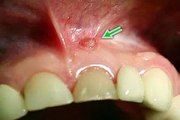

wsr ist die abkürzung für wurzelspitzenresektion. ein chirurgischer eingriff, der in der regel nichts bringt https://www.youtube.com/channel/UCtfezrProo8WbGBSwaEOMIA/search?query=wsr